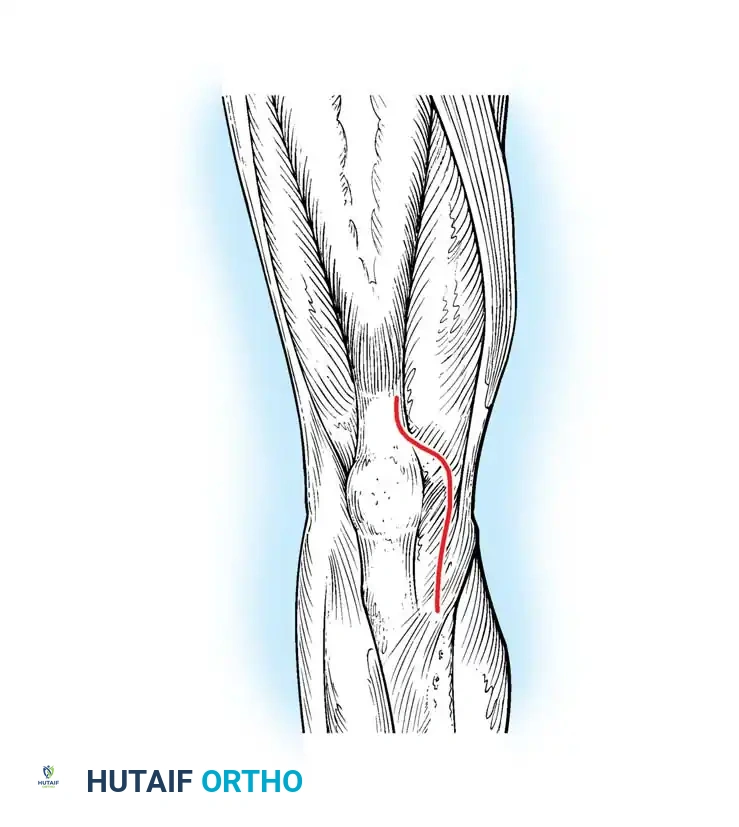

Surgical diagram illustrating the standard anterior midline skin incision transitioning into the deep medial parapatellar arthrotomy.

1. Skin Incision: A longitudinal midline incision is made, starting approximately 3-4 cm proximal to the superior pole of the patella, extending distally over the patella, and terminating just medial to the tibial tubercle.